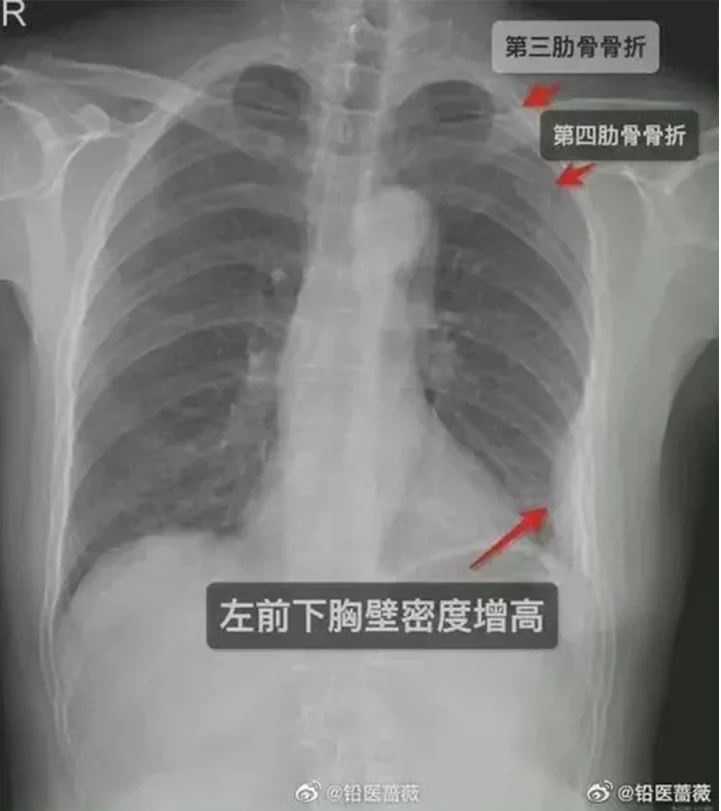

وبعد خمسة أيام من العناق الشديد، اشتد الألم إلى درجة كبيرة في صدر المرأة، وذهبت إلى المستشفى لإجراء فحص طبي، ليكشف فحص بالأشعة السينية تعرض 3 ضلوع لكسور، اثنان على الجانب الأيمن من قفصها الصدري وواحد على اليسار.